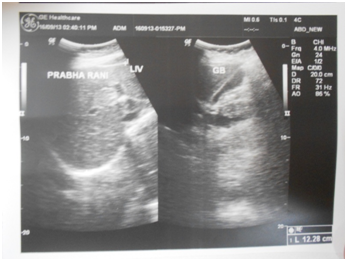

Conclusively, patients of asymptomatic and uncomplicated biliary sludge must be given chance to recover from their ailment by offering them “Srivastava regimen for biliary sludge” which contains oral ampicillin, UDCA and Phaltrikadi Kvatha (decoction) or Ghanbati (Tablet) for minimum of 45days, dietary fat restriction, plenty of water intake and avoiding all the possible confounding factors of gallstone diseases. In most of the patients, biliary sludge vanishes and gallbladder appears completely normal in ultrasonography (Figure 1) (Figure 2). Laparoscopic cholecystectomy remains gold standard treatment for complicated biliary sludge. In our opinion, one should try to avoid cholecystectomy in asymptomatic and even mild symptomatic cases as most of the patients give acceptable response to conservative management. By this we can not only avoid unnecessary expensive surgical burden to healthcare system but also save stress of our patients and not least poor gallbladder. We also want researchers to ponder further conclusive research trials which enable us better understanding of the pathogenesis of biliary sludge and further elucidation of the mechanism of action of these ayurvedic preparations at the molecular level for scientific basis of treatment. We have designed our regimen on the basis of available scientific researches and traditional ayurvedic literature and found that integrated approach of medicine works wonderfully and it is need of time.

Figure 2 Post-treatment ultrasonography scan showing clear gallbladder lumen.